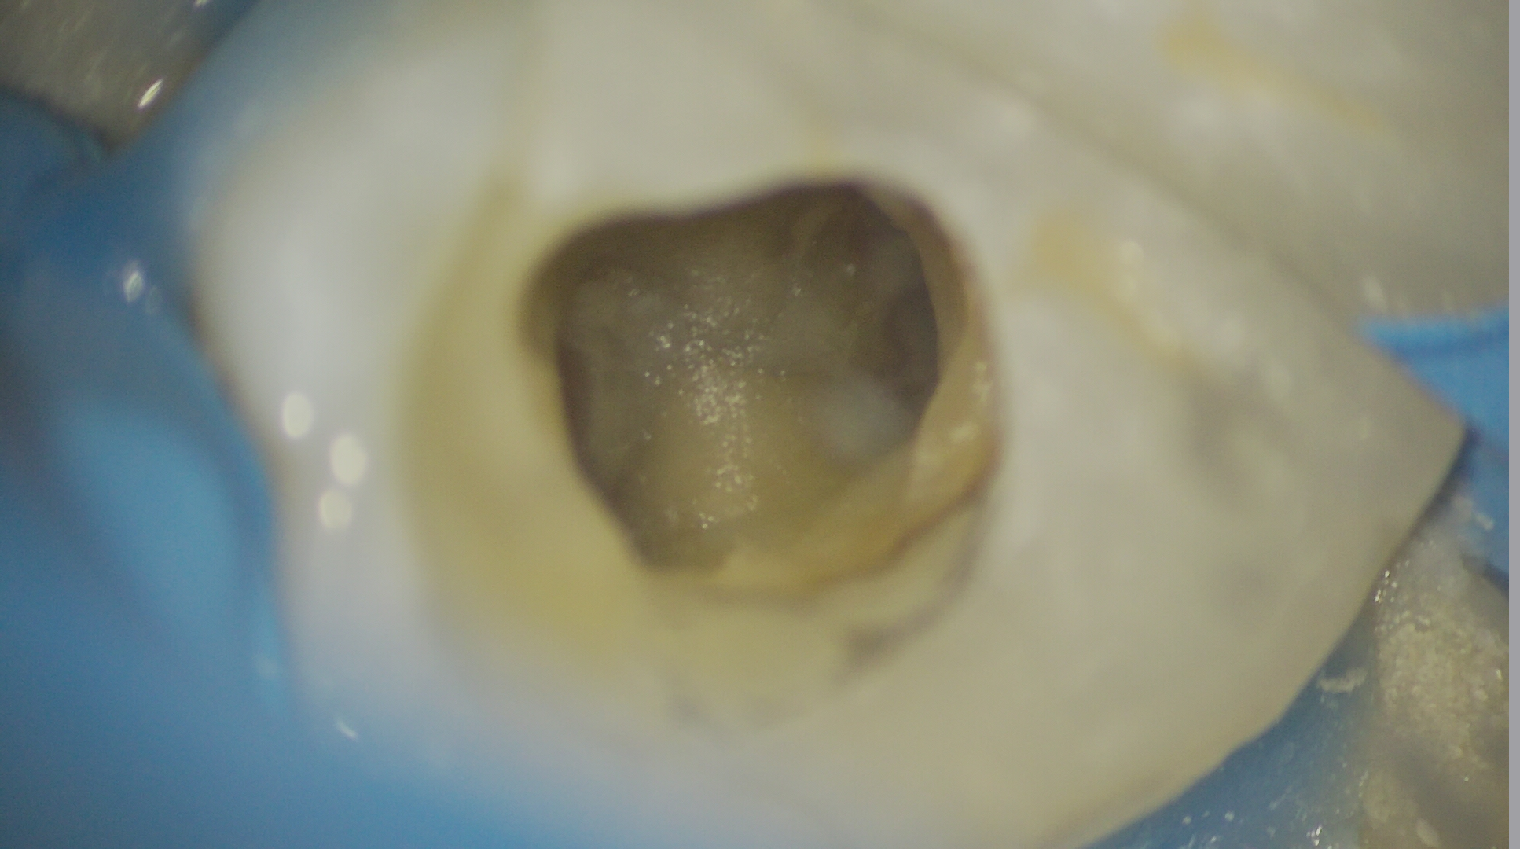

治療前

治療後